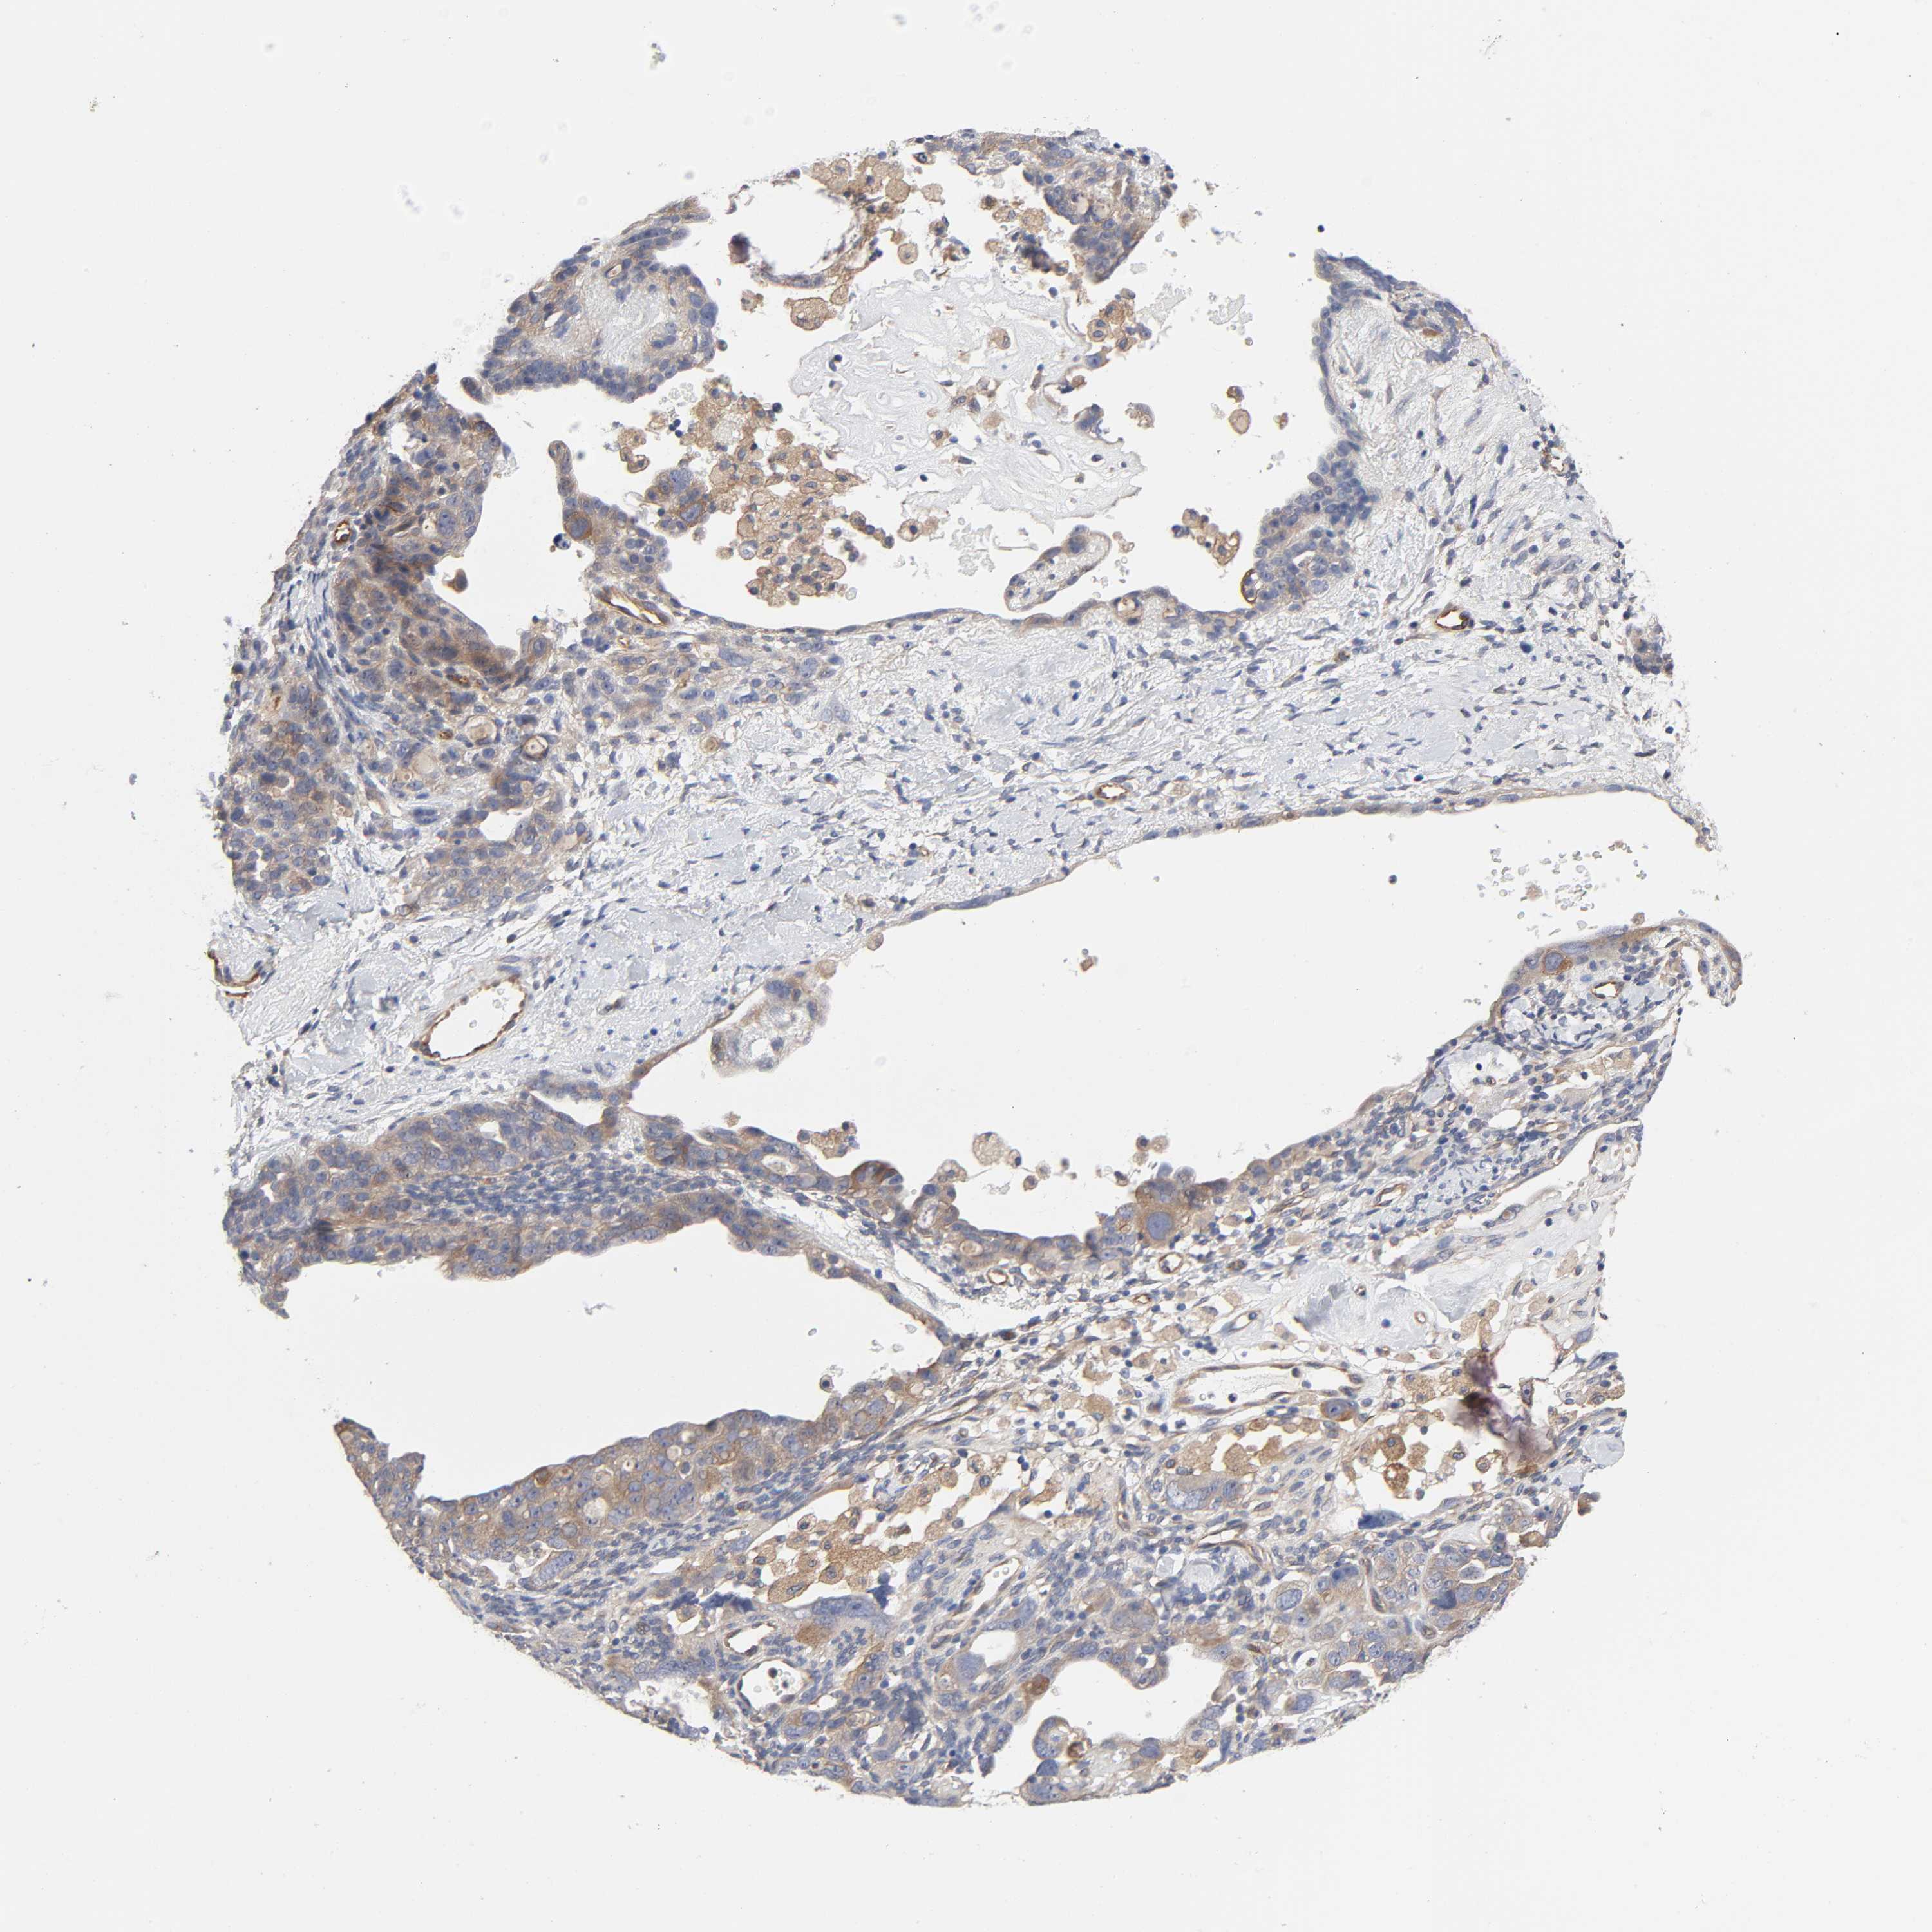

OVARIAN CANCER - Protein expressioni

A mouse-over function shows sample information and annotation data. Click on an image to view it in a full screen mode. Samples can be filtered based on level of antibody staining by selecting one or several of the following categories: high, medium, low and not detected. The assay and annotation is described here.

Note that samples used for immunohistochemistry by the Human Protein Atlas do not correspond to samples in the TCGA dataset.

Antibody stainingi

Antibody staining in the annotated cell types in the current human tissue is reported as not detected, low, medium, or high, based on conventional immunohistochemistry profiling in selected tissues. This score is based on the combination of the staining intensity and fraction of stained cells.

Each image is clickable and will lead to virtual microscopy that enables deeper exploration of all samples and also displays staining intensity scores, fraction scores and subcellular localization as well as patient and tissue information for each sample.

Antibody HPA003996

Staining

High

Medium

Low

Not detected

Intensity

Strong

Moderate

Weak

Negative

Quantity

>75%

75%-25%

<25%

None

Location

Nuclear

Cytoplasmic/membranous

Cytoplasmic/membranous,nuclear

Cystadenocarcinoma, serous, NOS

Cystadenocarcinoma, mucinous, NOS

Carcinoma, endometroid